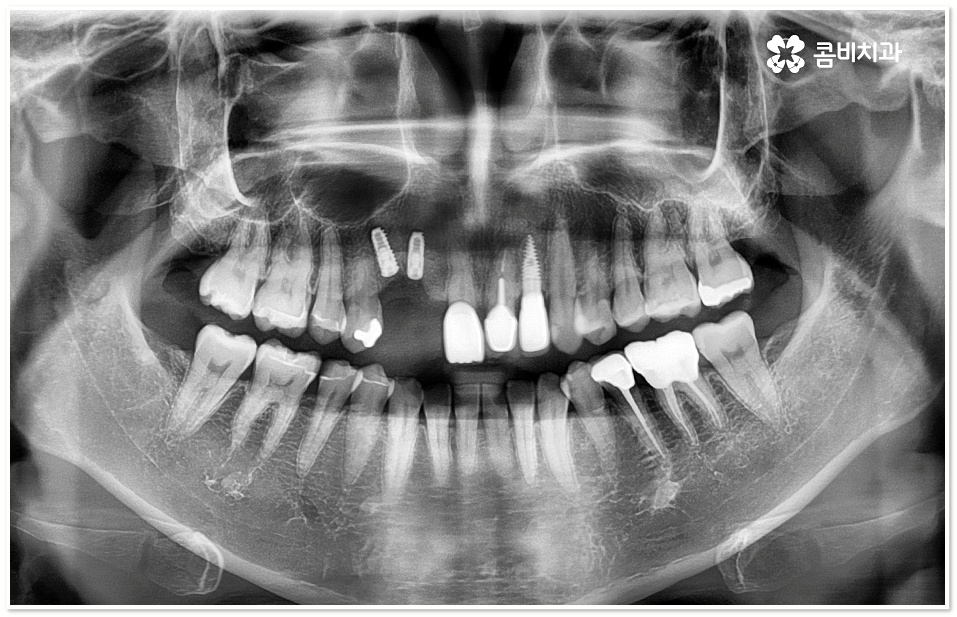

이러한 임플란트 시술을 활용하면 앞니, 어금니 등 어떤 부위의 치아 상실도 대체할 수 있지만 식립 부위의 특성을 고려해야 자연스러운 결과가 나오기 때문에 3D CT와 같은 정밀 진단 장비를 통해 시술해야 할 부분의 잇몸 건강 상태는 물론 신경 위치, 치조골 양, 주변 치아 구조 및 관계 등 여러 사항을 꼼꼼히 살펴보고 정확도 높은 시술 경로를 미리 확인하는 게 중요하다고 할 수 있는데요.

또한 앞니의 특성상 다른 치아보다 잇몸뼈가 얇고 폭이 좁으며 치조골 흡수가 잘 일어나기 때문에 환자분들의 상황에 따라서 잇몸뼈를 인공적으로 보충해야 하는 경우도 발생하는데, 이렇게 뼈이식 시술을 더하게 되면 치조골이 안정될 때까지 기다려서 식립을 진행해야 하기 때문에 보통 3개월 정도 걸리는 기간이 6개월 이상 늘어날 수도 있음을 감안하실 필요가 있습니다.

잇몸이 건강하고 치조골도 풍부하다면 치아를 발치한 후 바로 임플란트를 식립할 수 있지만 그렇지 않다면 식립 성공률이나 지속률을 높이기 위해서 뼈이식을 통해 바탕이 되는 부분을 충분하게 보충해 주는 것이 필요하므로 환자분들의 상황에 따라 앞니임플란트 시술 계획을 섬세하게 수립할 필요가 있어요.